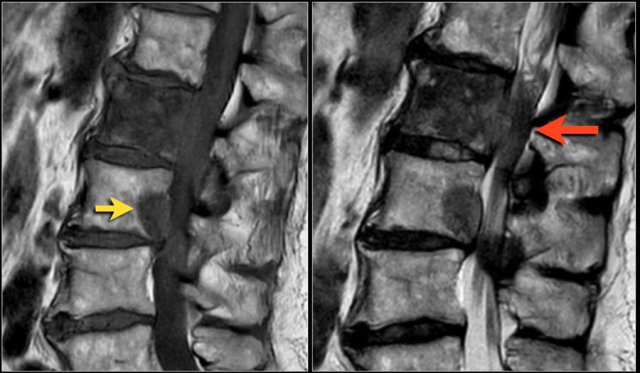

Here a disc herniation with upward migration.

By using the marker, you can correlate the abnormality on the T1W-image with the axial T2W-images.

On the T2W-image it is more obvious that this is a disc herniation.

The lower images are with the marker on.

you may have to enlarge the images to see it.

These foraminal disc herniations can be easily overlooked.

Notice how subtle the findings are on the axial T2W-images.

The herniated disc can be easily mistaken for the nerve root.

The sagittal T1W-image shows the upward migration of the disc.